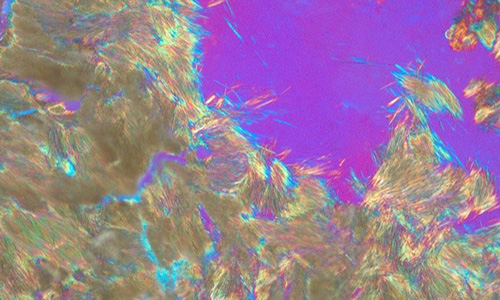

NIH (NIAMS)   —   R21AR078498

Apte, Suneel

“The proteolytic landscape of osteoarthritic cartilage”